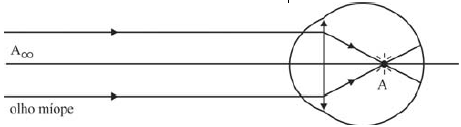

O olho é um dos principais órgãos sensoriais do ser humano. Ele é composto por um conjunto complexo de meios transparentes, regiões fotossensíveis e nervos. Para entender o olho do ponto de vista puramente físico, criou-se o modelo do “olho reduzido”, em que o olho é considerado como uma lente convergente com distância focal variável. Algumas definições foram criadas para representar os limites do olho humano. O ponto máximo representa a maior distância da lente em que o olho é capaz de enxergar. O ponto mínimo representa a menor distância em que o olho consegue enxergar (em torno de 25 cm).

Um olho míope tem maior excentricidade no globo ocular, de tal forma que as imagens são formadas antes da retina. Para se corrigir um olho míope, empregando-se uma lente de raio de curvatura igual a 0,4 m, devem ser usadas